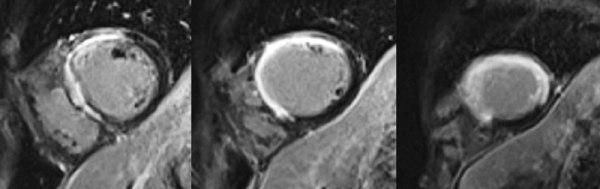

Figure 2A : Séquence de perfusion premier-passage au repos - Coupes petit-axe médian

Figure 2B : Séquence de perfusion premier-passage au repos - Coupes 2-cavités

Figure 2C : Séquence de perfusion premier-passage au repos - Coupes 4-cavités

Présence d’une hypoperfusion sous-endocardique de toute la paroi antéro-septo-apicale débordant sur la paroi apico-latérale. Cette hypoperfusion correspond à la zone de l’infarctus.

Aucun thrombus intra-VG n’est visualisé sur ces séquences de perfusion de premier passage de repos. En effet, un thrombus serait apparu sous la forme d’une masse apicale en hyposignal (noire) avec un produit de contraste qui aurait moulé le thrombus.